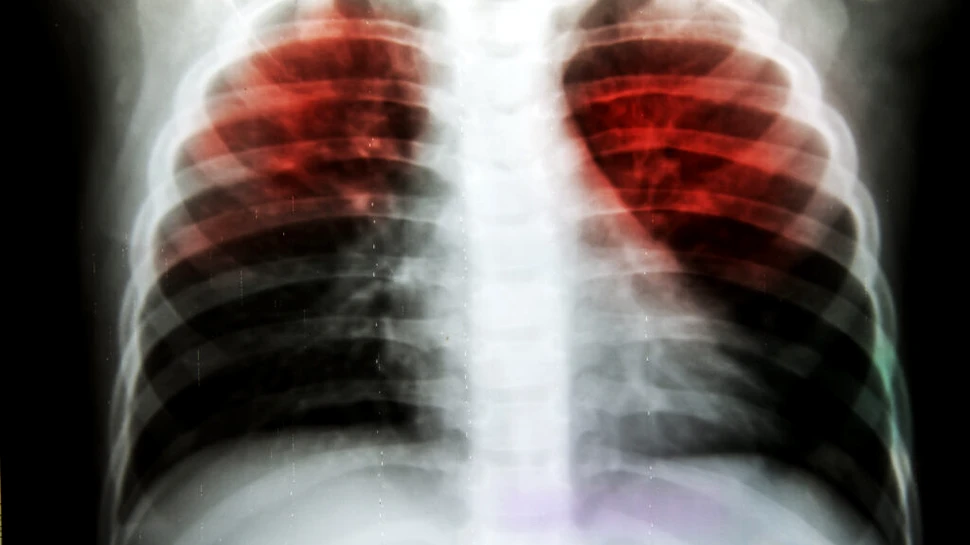

Un test de sânge care ar putea identifica milioane de persoane care răspândesc tuberculoza (TBC) fără să știe este aproape de a fi dezvoltat, oferind o speranță majoră pentru combaterea acestei boli mortale.

Tuberculoza, sau TBC, este cea mai mortală boală infecțioasă din lume și ucide peste un milion de persoane în fiecare an, potrivit datelor Organizației Mondiale a Sănătății.

Se răspândește prin inhalarea picăturilor mici din tusea sau strănutul persoanelor infectate. Afectează în principal plămânii, dar poate afecta și alte părți ale corpului.